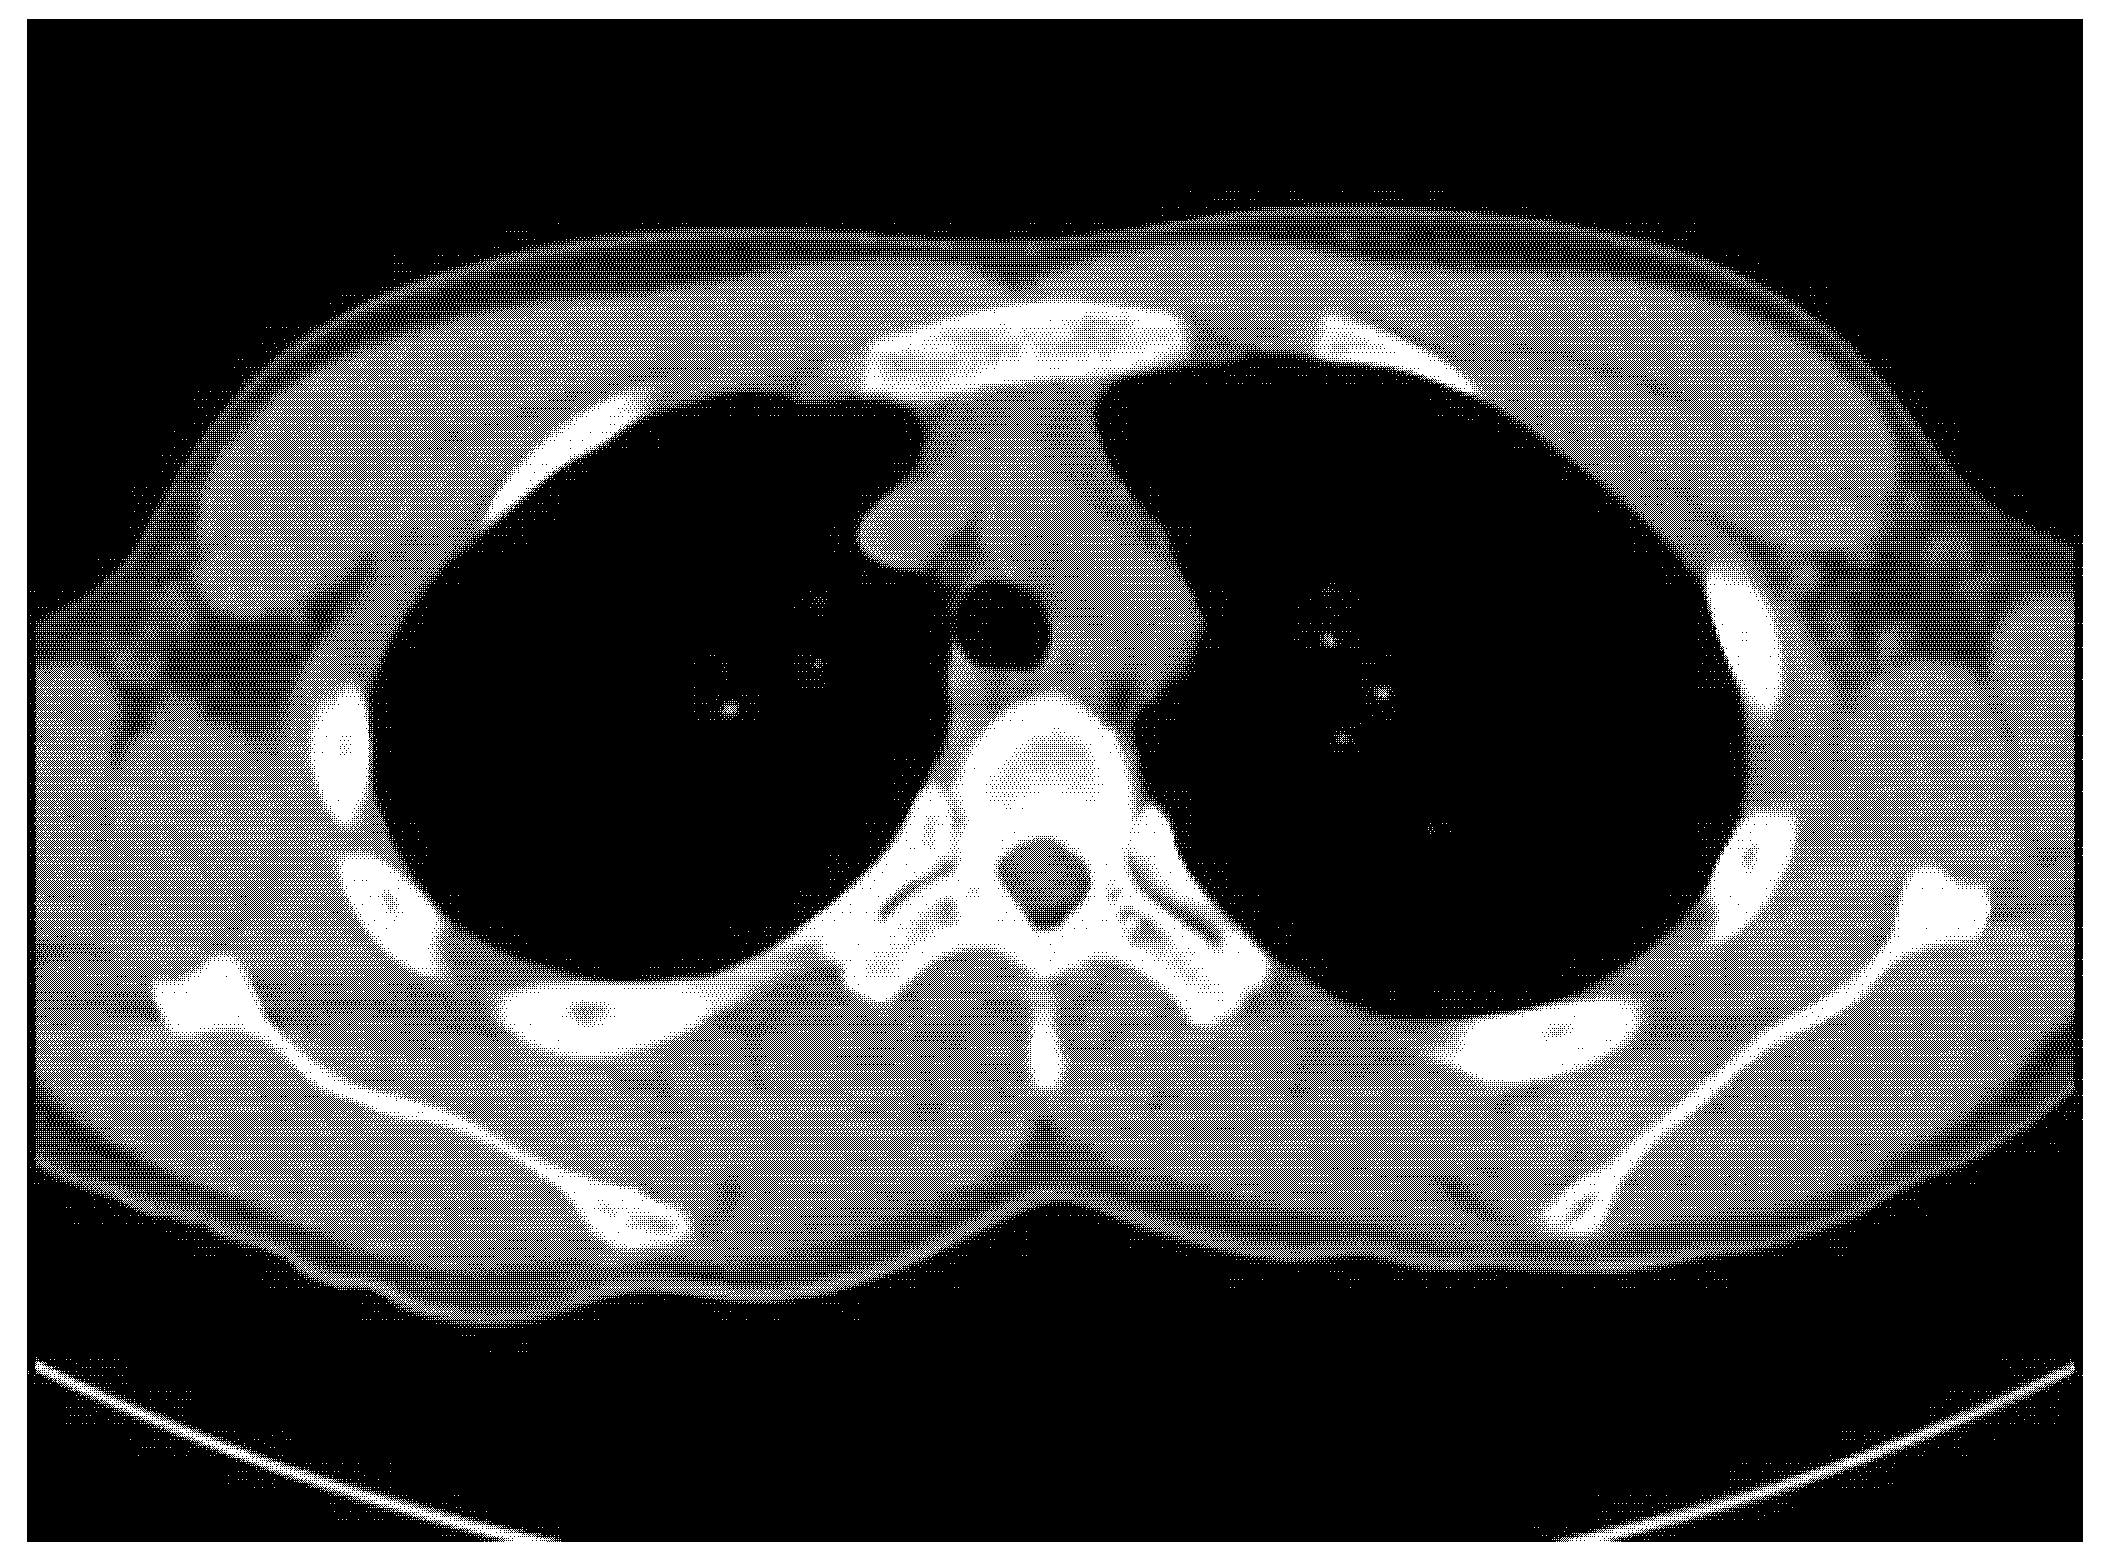

Usually, we do not perform a biopsy when MO is suspected. However, in this case, the patient’s symptoms worsened, and its location was unusual for MO, so both the clinician and patient strongly wanted to perform a biopsy. Therefore, to confirm the diagnosis and exclude the possibility of malignancy, we decided to perform a US-guided biopsy. In the US, hyperechoic peripheral rim calcification with posterior shadowing was noted (Figure 4). A US-guided needle biopsy was performed, and the pathological report confirmed myositis ossificans with zone phenomenon (Figure 5).

Figure 4. In the US, calcified peripheral rim and posterior shadowing were noted. A US-guided biopsy was performed.